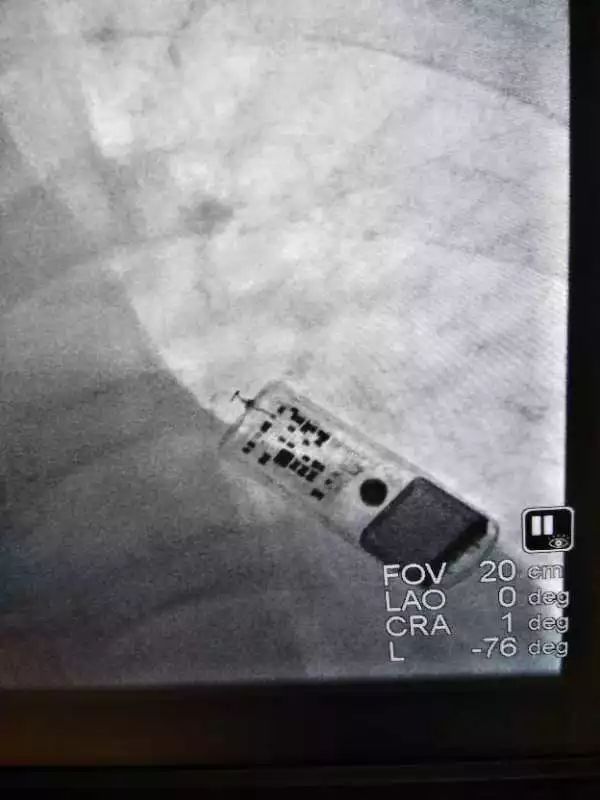

近日,南通瑞慈醫(yī)院心內(nèi)科成功為一位高度懷疑心源性暈厥的患者完成了皮下心電監(jiān)護(hù)儀植入手術(shù)。這種植入式心電監(jiān)護(hù)儀僅有U盤大小,可以連續(xù)三年追蹤記錄患者的心電信息,為明確暈厥原因提供可靠參考。

8月7日下午,南通瑞慈醫(yī)院副院長、心內(nèi)科郭艾武主任為患者順利實(shí)施了手術(shù)。手術(shù)過程非常順利,醫(yī)生花了不到15分鐘時(shí)間就完成了整個(gè)過程。僅在患者左側(cè)胸部肋間的皮下進(jìn)行局部麻醉,通過近2厘米的小切口,將監(jiān)護(hù)儀植入皮下。術(shù)中術(shù)后檢測,監(jiān)護(hù)儀均工作正常。

未來三年內(nèi),這枚心電監(jiān)護(hù)儀將在患者體內(nèi)堅(jiān)守工作崗位,持續(xù)動(dòng)態(tài)地記錄患者的心律狀況。

植入式心電監(jiān)護(hù)儀里設(shè)有數(shù)據(jù),一旦患者的心電信息達(dá)到了病發(fā)標(biāo)準(zhǔn),記錄儀就會(huì)自動(dòng)觸發(fā)進(jìn)行記錄。

另外,患者如果自身感到不適,也可以按動(dòng)配備體外的按鈕“開關(guān)”,主動(dòng)觸發(fā)記錄心電事件。醫(yī)生則可以通過體外“遙控器”,調(diào)出植入式心電監(jiān)護(hù)儀里儲(chǔ)存的信息,運(yùn)用最直觀的數(shù)據(jù)進(jìn)行原因分析。